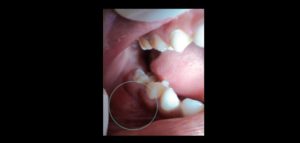

185 – Manejo endodóntico del dens invaginatus Tipo IIIB